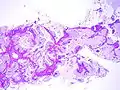

Mucinous BAC

Non-mucinous BAC